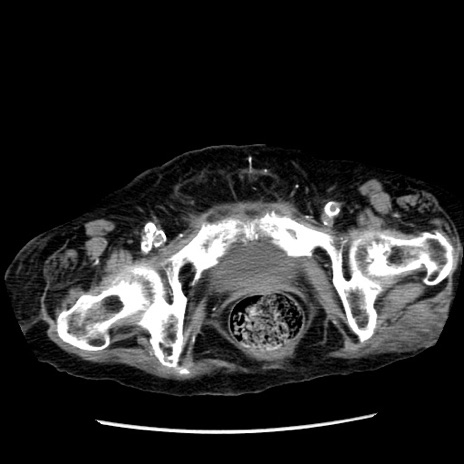

症例14(横断像)

【症例】 90歳代女性

【主訴】 腹痛・嘔吐

【現病歴】今朝から左側腹部痛を認めた。 経過観察していたが、嘔吐を認めたため来院。

【既往歴】 子宮癌術後

【身体所見】 意識清明、BP 127/54mmHg、P 98bpm Sp02 95%(RA)、BT 35.8°C、腹部平坦・軟腸ぜん動音聴取良好、右下腹部圧痛(+) 反跳痛なし

【データ】WBC 9800、CRP 0.46